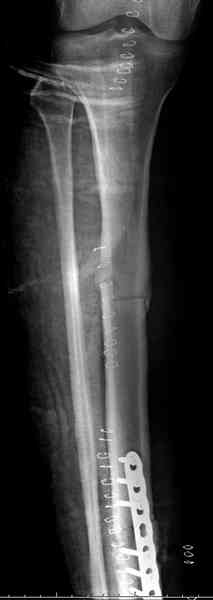

Недавно на нашей ежемесячной Morbidity&Mortality conference мы

разбирали похожий случай, ложный сустав большеберцовой кости после

резекции опухоли.

Оперирован в военном госпитале с заменой сегмента аллокостью

большеберцовой кости и после демобилизации явился для постоянного

наблюдения по месту жительства.

Наши имели проблему со сращением, пришлось им сделать динамизацию,

дополнительную аутопластику.

Снимки представлены.

Имя     : 3 adamantioma ap prox plate.jpg